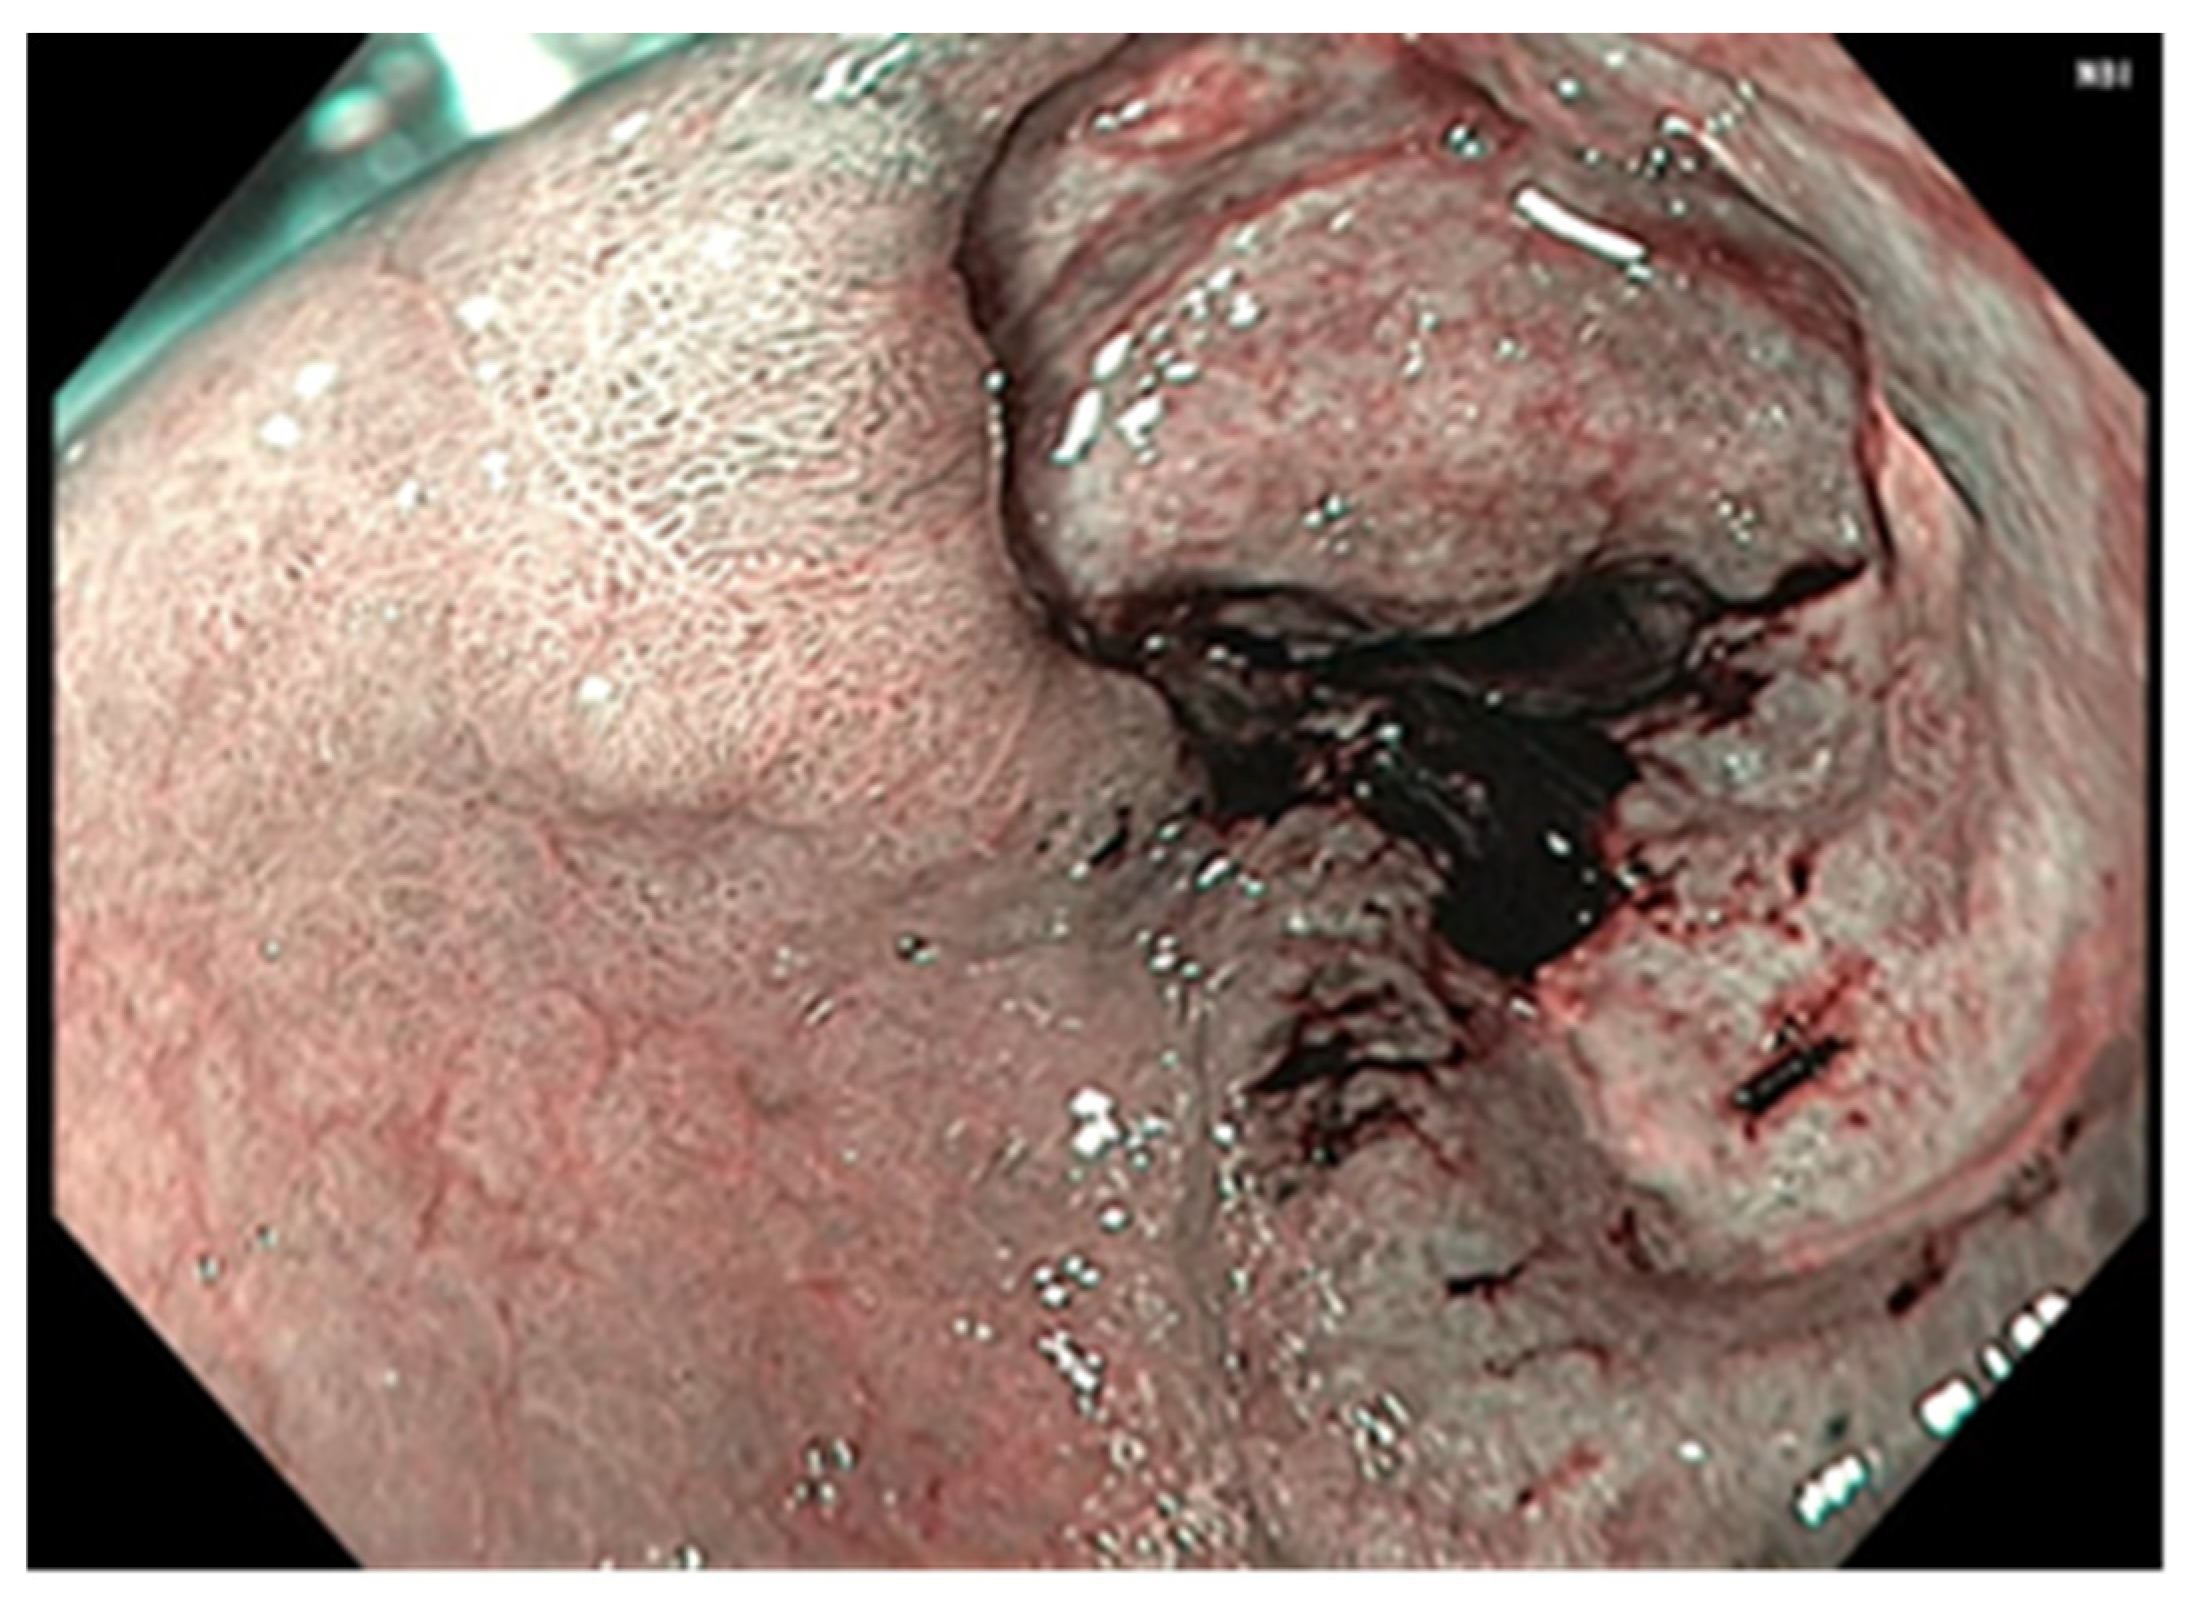

3. Results

3.2. Treatment Particularities